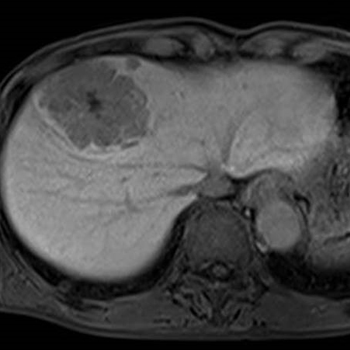

7. 간암의 초기증상 및 증상

간암의 경우 알려진 초기증상은 거의 없지만, 드물게 담관 주위에 암이 생기면 초기 무렵부터 황달이 보일 수 있습니다.

암이 간 내에서 어느 정도 진행하여 커지게 되면, 발열과 복수, 혈관의 팽창 등의 증상이 발생합니다. 또한 담관이 막히면서 황달이 보이는 특징이 있으며, 이런 증상이 나타나면 치료를 하더라도 생존율은 매우 적습니다.